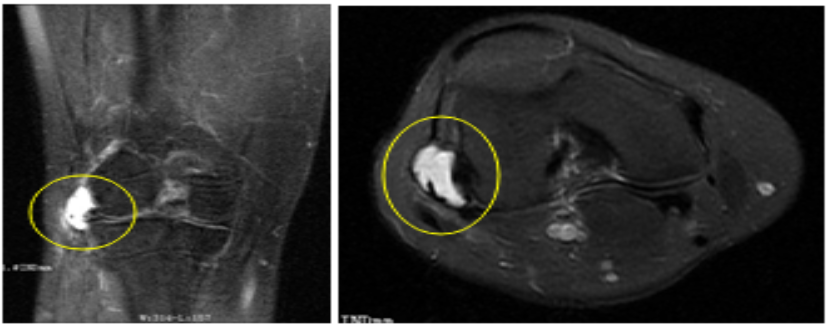

2020年3月3日,州人民医院康复科收治一位35岁女性患者,诊断为“右膝外侧半月板囊肿”。该患者在10年前因“左膝囊肿”在其他医院做过传统开放性手术。患者入院后,经骨科吴俊一主任医师会诊后,转入骨科手术治疗。

患者转入骨科后,经积极完善术前准备和骨科全科医师讨论,于2020年3月12日,由骨科关节镜手术治疗的专家蒲俊贵副主任医师主刀行“右侧膝关节关节镜下关节腔清理+半月板囊肿内引流+外侧副韧带修复术”。术后患者右膝疼痛明显缓解,早期即可下床活动。